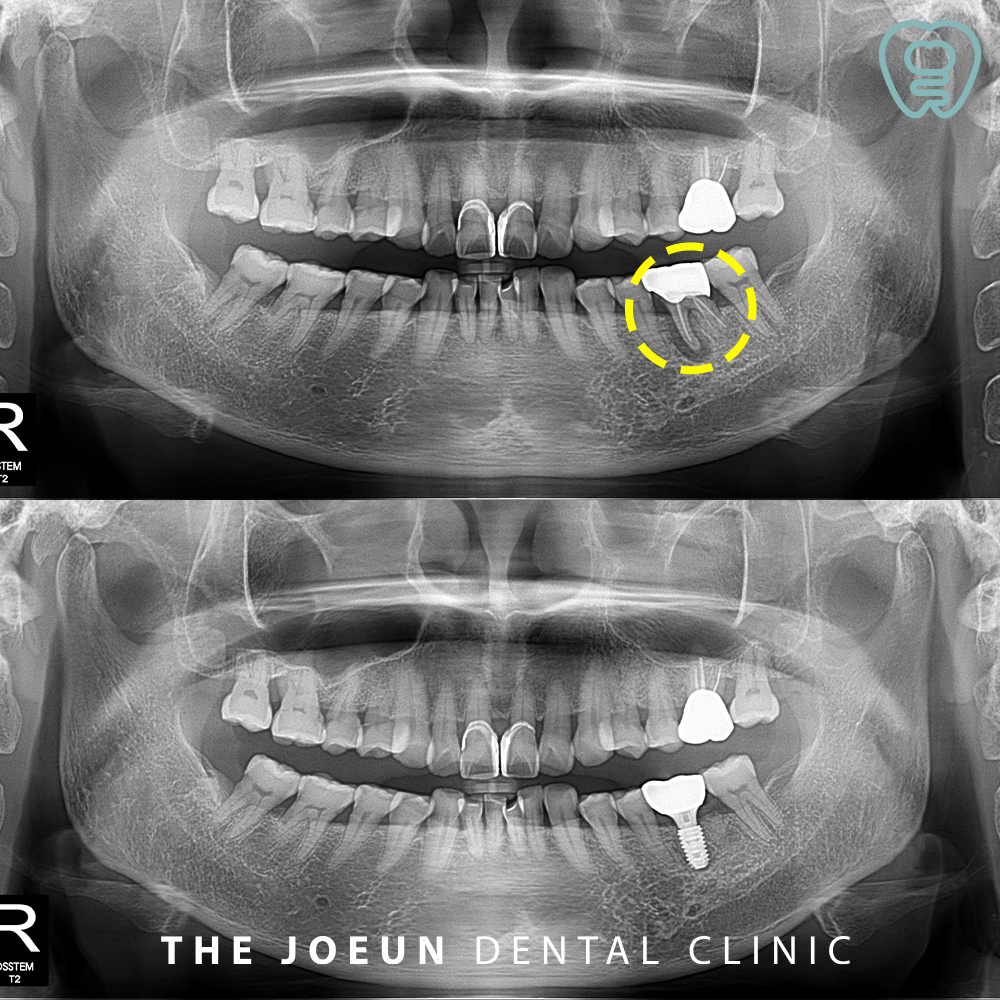

환자분께서는 오래 전 씌워둔 왼쪽 아래 어금니 부위가 씹을 때 힘이 들어가지 않고 잇몸이 붓는 느낌이 있으시다며 내원해 주셨는데요. 파노라마 촬영 시, 왼쪽 아래 첫번째 큰 어금니 뿌리에 커다란 염증이 관찰되었고 이미 치료가 되어 있는 상황이라 발치 후 임플란트 치료를 설명드린 후 진행하기로 하였습니다.

발치 후 치아 뿌리에 붙여 있는 염증 덩어리가 명확히 확인되었는데요. 잇몸뼈의 골질이 약하다고 판단되어 임플란트 식립 후 충분한 기간을 기다려준 뒤 최종 보철물을 진행하는 것으로 하였습니다.

약 4개월 뒤, 잇몸뼈와 인공치근의 고정력을 확인한 뒤 최종 보철물을 완성하였습니다.